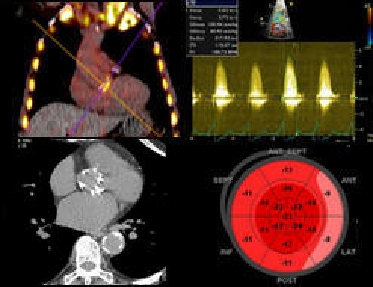

Aortic Stenosis image